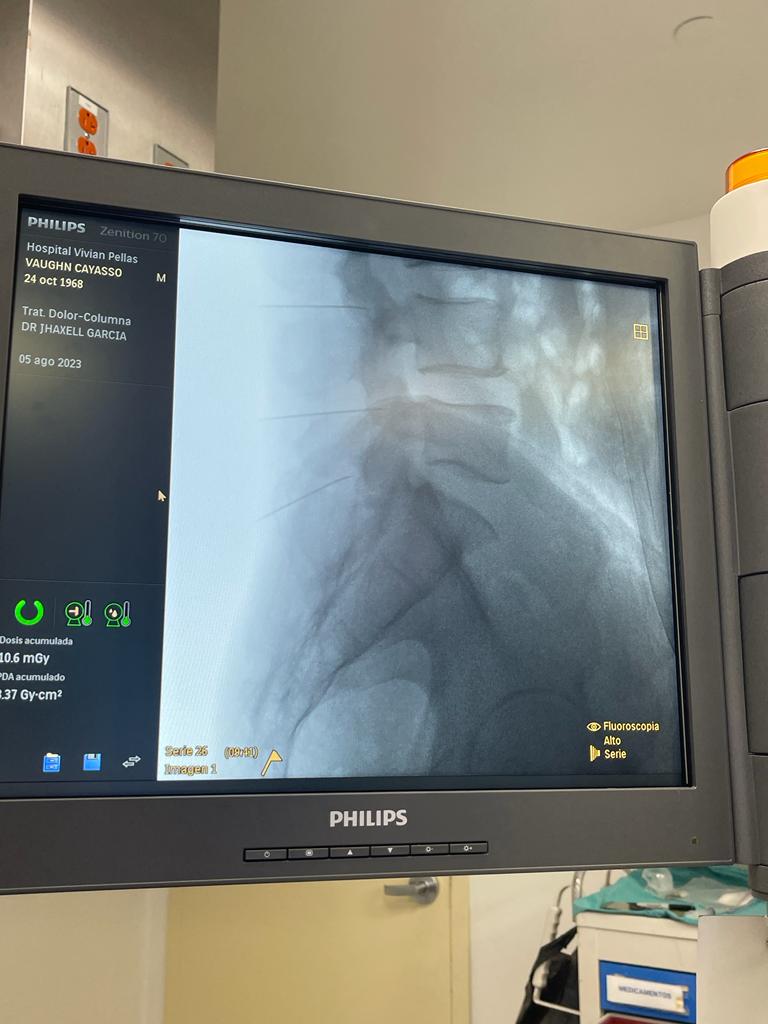

Rizólisis (Ablación por Radiofrecuencia)

Técnica mínimamente invasiva para tratar el dolor crónico articular de la columna

¿Qué es?

La rizólisis es un procedimiento no quirúrgico que utiliza energía de radiofrecuencia para inactivar de forma selectiva los nervios responsables de transmitir dolor desde las articulaciones facetarias de la columna.

¿Para quién está indicada?

- Pacientes con dolor lumbar o cervical crónico, de origen mecánico

- Artrosis o degeneración de las articulaciones facetarias

- Dolor que no responde a tratamiento conservador (analgésicos, fisioterapia, bloqueos)

- Personas que no son candidatas a cirugía mayor

Beneficios

- Procedimiento ambulatorio

- Bajo riesgo de complicaciones

- Mejora del dolor durante meses (en ocasiones más de un año)

- Puede repetirse si reaparecen los síntomas